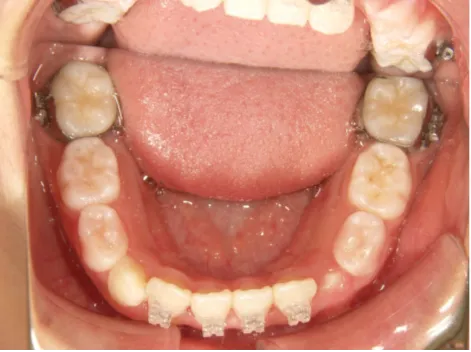

治療中➁小3:9y8m QH、BH、前歯並び替え終了

モノブロック装置(筋機能的咬合誘導装置)スタート